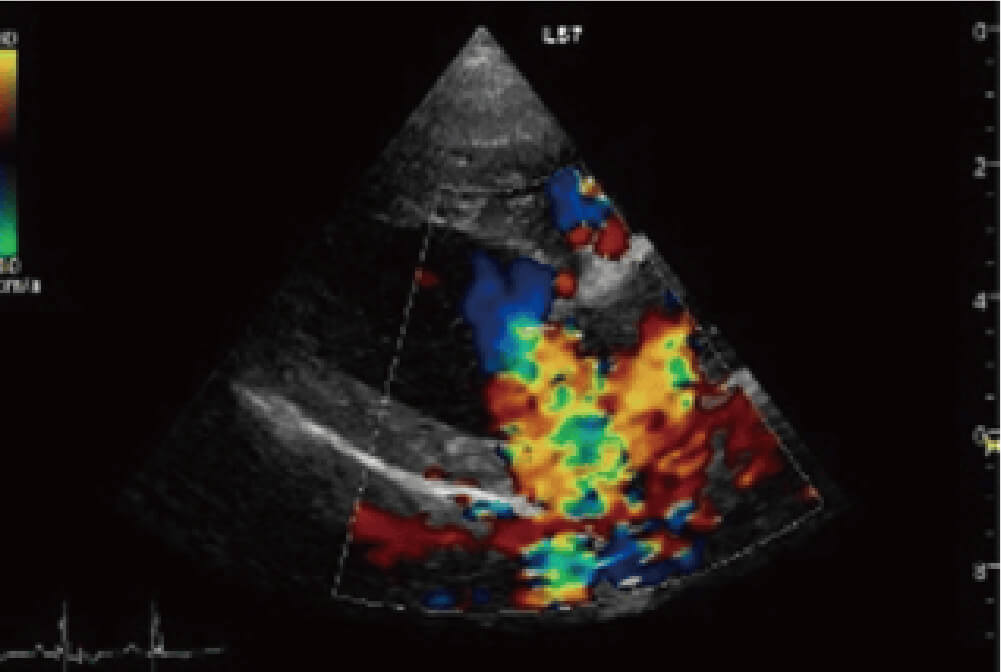

左図は僧帽弁形成術前の心臓超音波画像(右傍胸骨長軸四腔断面像)。Carpentier’s functional classification typeⅡの特徴である弁尖の逸脱が前尖・後尖共に見られます。またカラードプラ画像では重度の僧帽弁逆流がみられます。